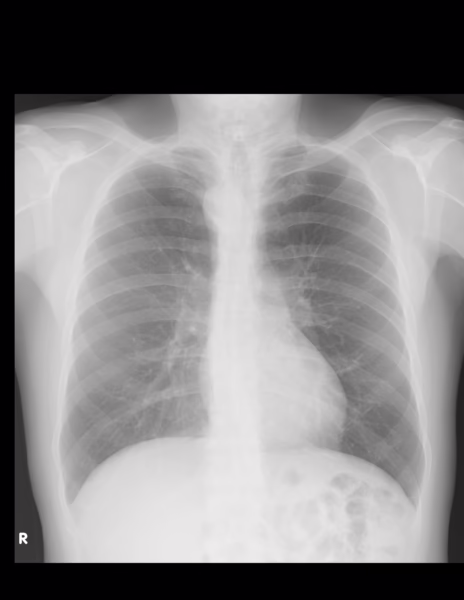

Se identifican los tejidos blandos y oseos de densidad homogénea, osteofitos incipientes vertebrales.

El cardiomediastino muestra un índice cardiotorácico en límites normales, se observa arco aórtico hacia la derecha, el flujo vascular pulmonar se considera normal.

No hay evidencia de infiltrados o consolidaciones pulmonares.

Los hemidiafragmas de apariencia normal, los ángulos cardiofrenicos y costodiafragmaticos se observan libres.

IMPRESIÓN DIAGNOSTICA:

Osteofitos incipientes vertebrales, arco aórtico hacia la derecha.